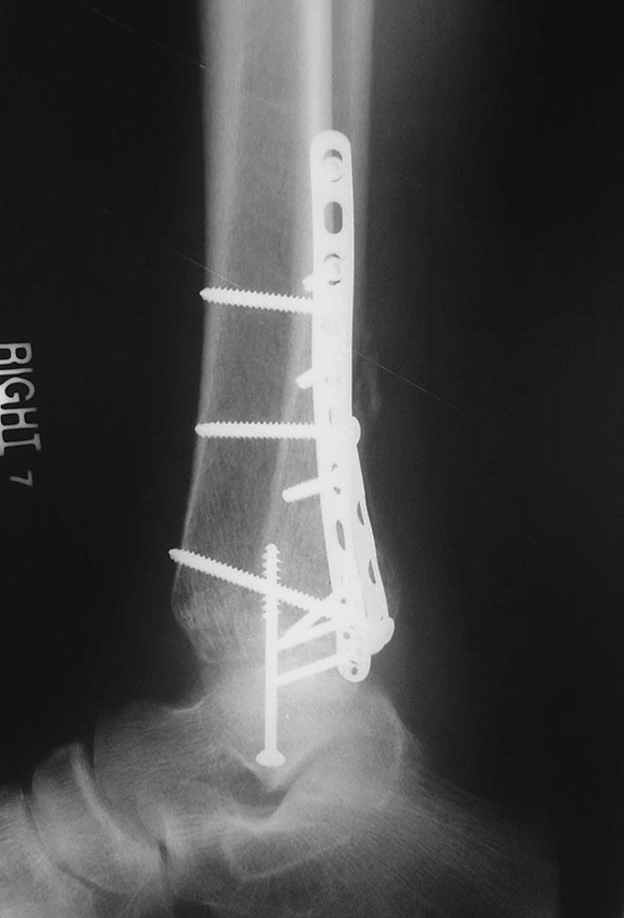

Второй случай сделан из одного разреза

ЕЧ LISS plate, mininvasive approach - luxurous !

На прямой проекции послеоперационного Рг макроскопически все выглядит очень анатомично, при микроскопическом ( :-)) ) рассмотрении можно все-таки заметить вальгизацию тарана, суставная щель в латеральном отделе сустава несколько уже , чем в медиальном при отсутствии латерального смещения тарана. У меня был аналогичный случай (без LISS , без мини доступа) с вальгусным наклоном тарана при восстановленном ankle mortise при последовательном наблюдении с интервалами в 6-8 недель в послеоперационном периоде отмечалось прогрессирующее сужение суставной щели в латеральном отделе сустава, закончившееся посттравматическим ОА, к счастью боли умеренные, купируемые аналгетиками или своими эндорфинами:-))(активная пациентка, у которой нет времени на болезни....) Какова жизненная ситуация в приведенном вами случае? И последнее, что я хотел бы прояснить для себя - фиксация внутренней лодыжки: я обычно комбинирую фиксацию компрессирующим винтом со спицей - по идее ротационная стабильность должна быть лучше, чем один винт, каковы ваши наблюдения в этом плане?